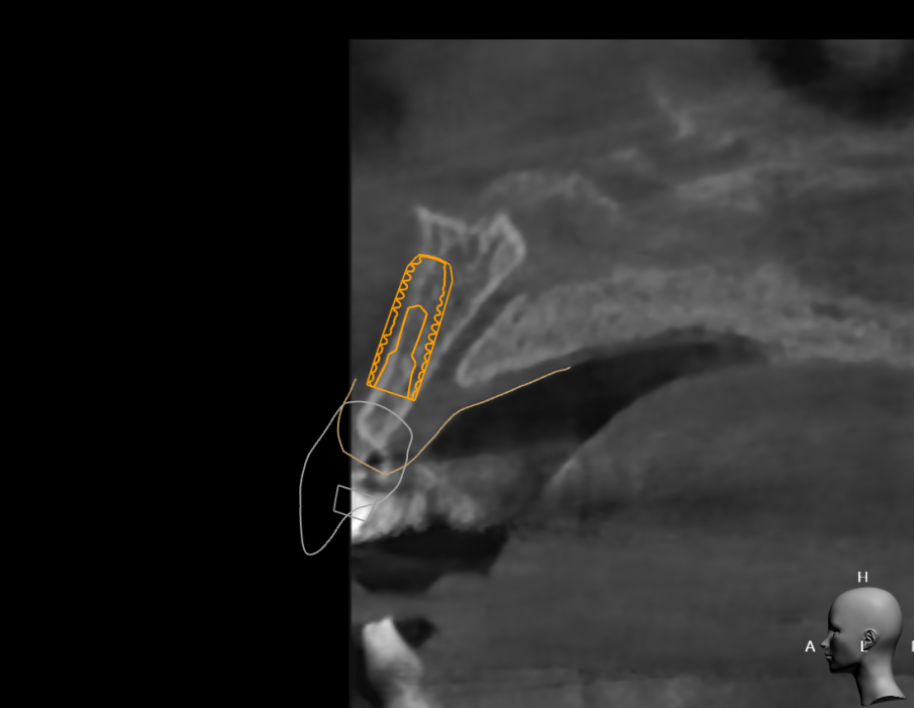

ct 촬영을 통해 남아있는 잇몸뼈를 분석하고

디지털 임플란트 기술로

위치, 식립 깊이, 두께 등

예측 수술도 진행했습니다.

분석된 결과물입니다.